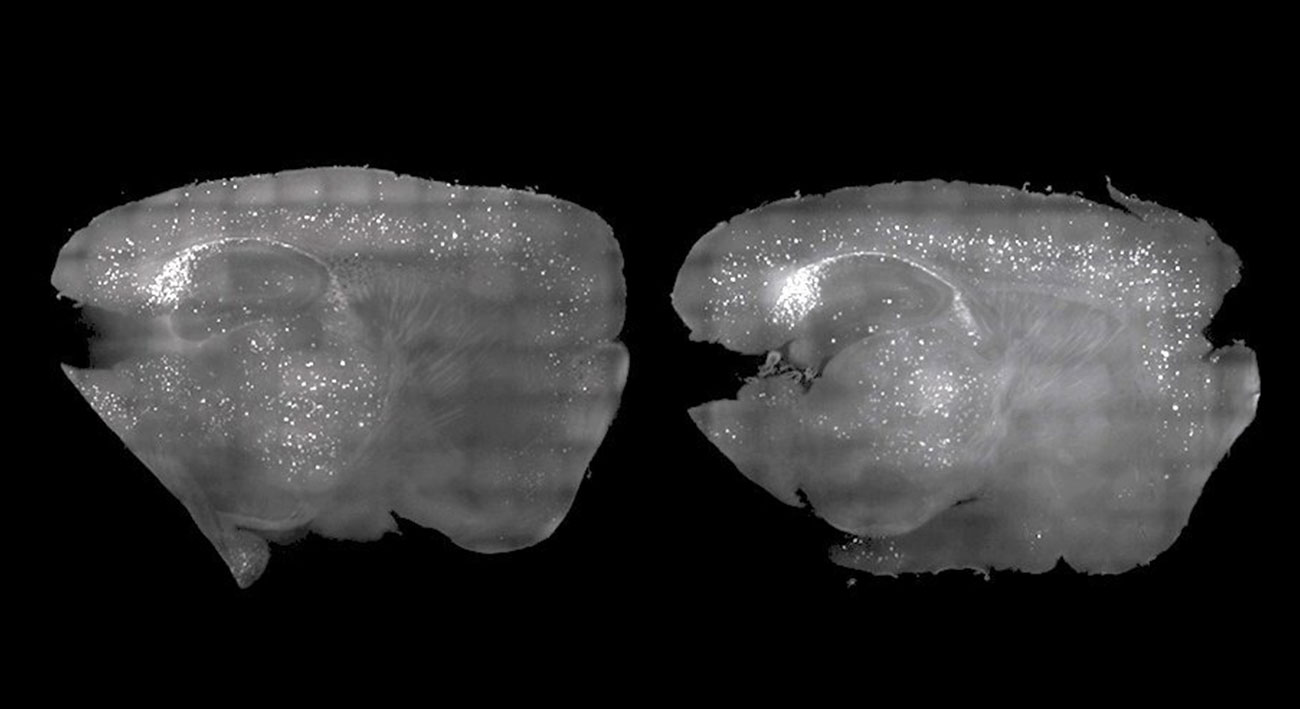

Амилоидные бляшки, которые мешают работе мозга мышей, удалили с помощью звуков. В будущем эти опыты могут привести к появлению дешевого и безлекарственного способа лечения нескольких форм деменции.

Исследования, проведенные в MIT, показали, что стробоскопические лампы и низкочастотное жужжание можно использовать для воссоздания мозговых волн, потерянных при болезни. Также этот метод позволяет удалить часть амилоидных бляшек, которые могут образоваться в мозгу.

Гамма-волны прекращаются или замедляются при некоторых болезнях — например, у людей с Альцгеймером. Вспышки света и низкое жужжание же могут индуцировать гамма-колебания в мозге, уничтожая амилоидные бляшки в его префронтальной коре. В MIT отметили, что мыши, после этих процедур, значительно лучше справлялись с несколькими когнитивными задачами.